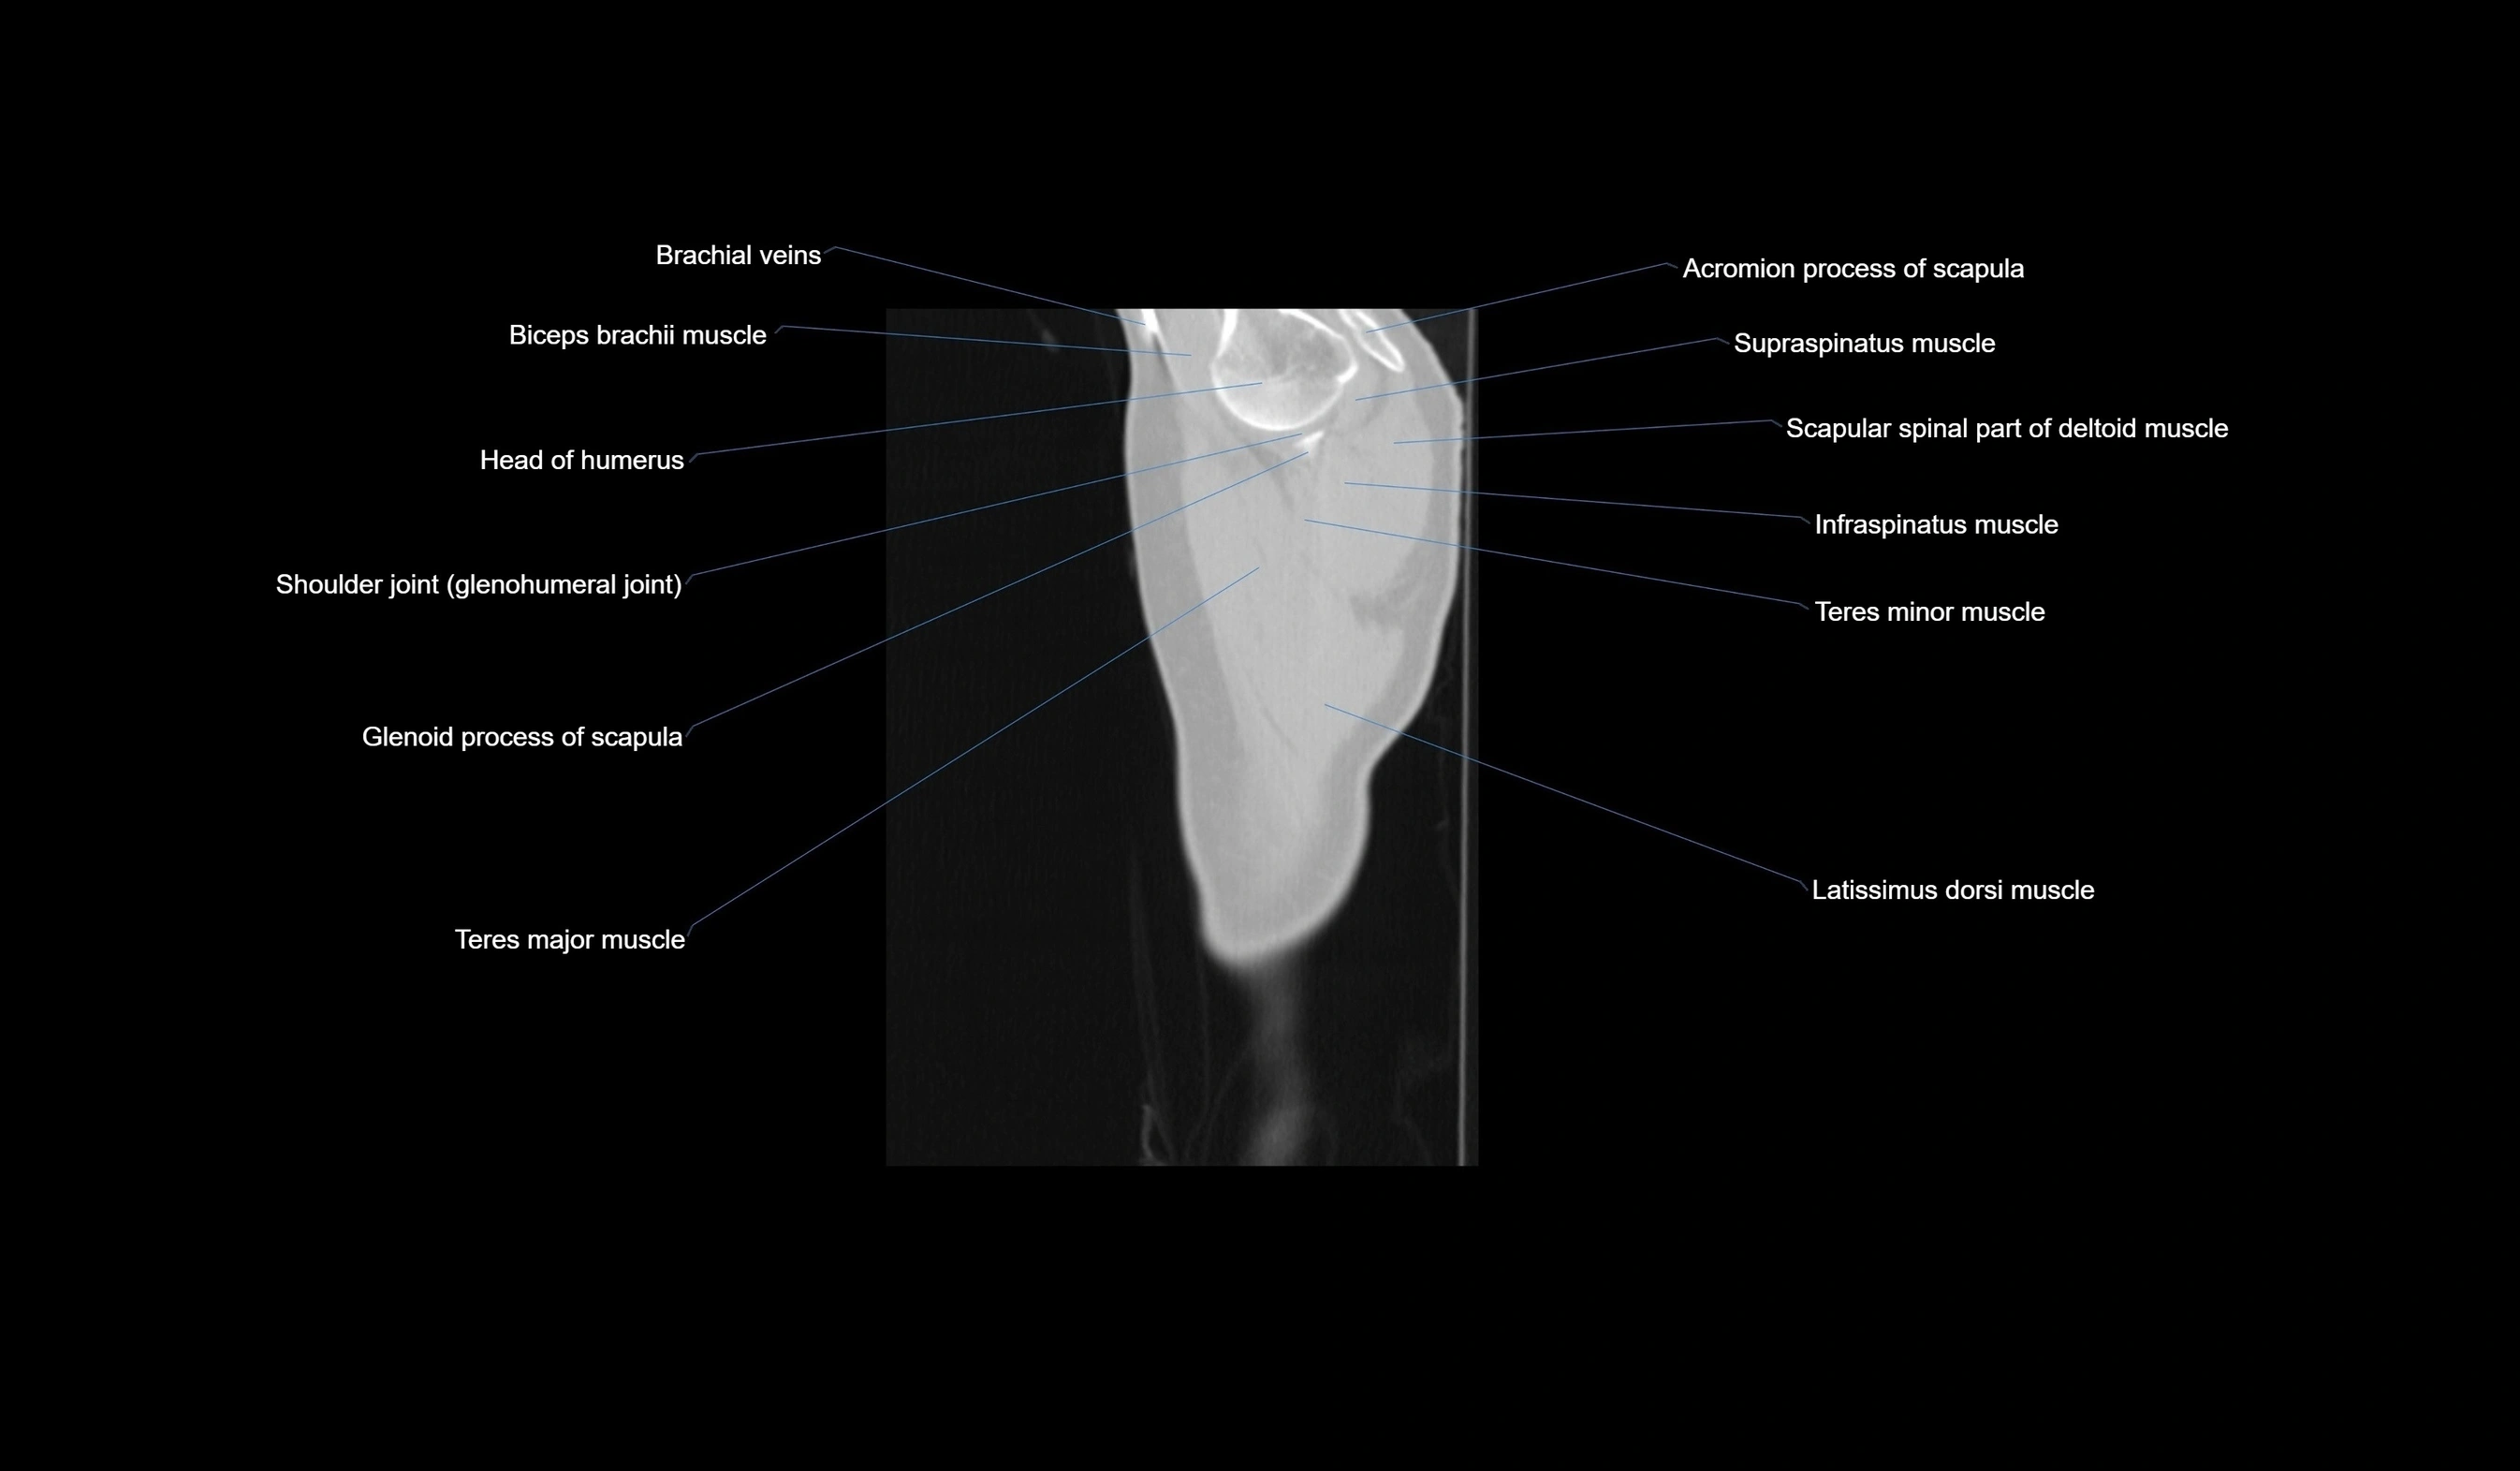

- Acromion process of scapula

- Articular cartilage of glenoid fossa

- Biceps brachii muscle

- Brachial veins

- Glenohumeral joint

- Glenoid process of scapula

- Head of humerus

- Infraspinatus muscle

- Latissimus dorsi muscle

- Shoulder joint (glenohumeral joint)

- Supraspinatus muscle

- Teres major muscle

- Teres minor muscle